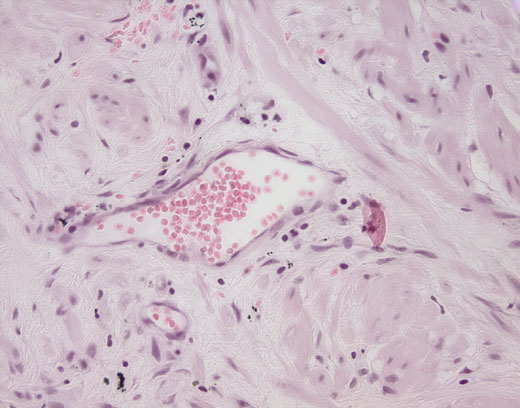

Cross-section #51 - 40X